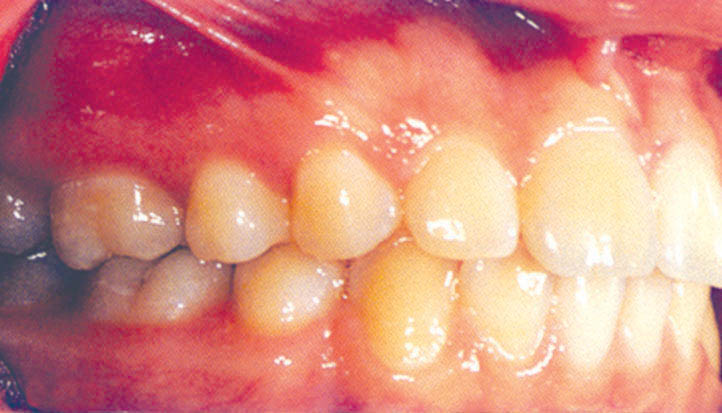

4. دندان 4 بالا که بجای 3 قرار میگیرد: اگر کانین کشیده شده (شکل 88-1) یا missing لترال دارید و کانین را بجای لترال قرار دادهاید (شکل 89-1) براکت 4 را 0.5mm دیستالیتر بچسبانید تا دیستال آن باکالیتر شود و حالت برجستگی کانینی ایجاد نماید.

ترتیب دندانها در انتهای درمان این بیماران به صورت سانترال، کانین و پرمولر میشود. با نگاه به لثه آنها میبینید که مارجین لثه ارتفاع خوبی ندارد. چون همیشه لترال بین سانترال و کانین است و لثه آن ارتفاع پایینی دارد در حالی که در این بیماران کانین بین سانترال و پرمولر قرار گرفته و مارجین آن بالاتر و مارجین پرمولر پایینتر است بهتر است در این گونه بیماران برای زیبایی بیشتر لثه، براکت کانین را 1mm ژنژیوالیتر و پرمولر اول را 1mm انسیزالیتر بچسبانید تا با اکسترود و اینترود نسبی این دندانها لثه زیباتر به نظر بیاید. در انتهای درمان حتماً با کارهای ترمیمی فرم تاج را زیباتر کنید.

شکل 88-1: دندان کانین بیمار کشیده شده و پرمولراول حکم کانین را دارد.